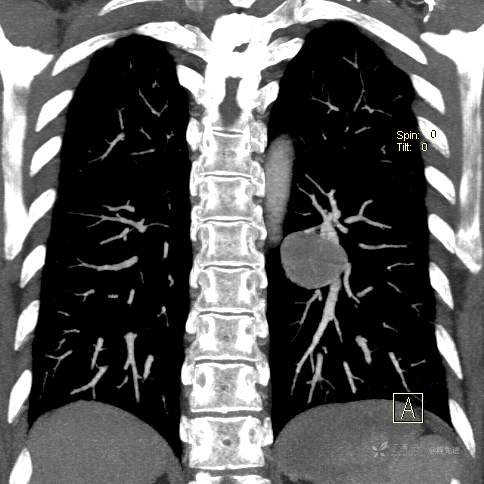

患者性别:女

患者年龄:57岁

简要病史:体检发现

CT增强

平扫CT值约40HU(未上传图像),增强后动脉期CT值约70HU,静脉期CT值约97HU。

肺硬化性血管瘤 (20)